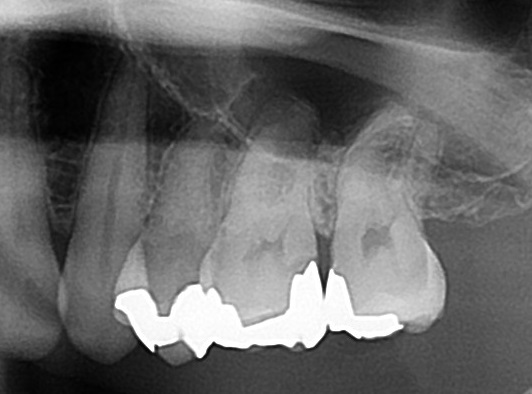

上記写真の親知らずの場合、親知らず自体が黒くなっているのが分かりますが、さらにレントゲン写真(エックス線)検査で歯の中の状態を見てみると

エックス線検査は見えない歯の内部が見えます。横向きに生えて、手前の歯にぶつかっているのが分かります。

こちらをよく見てみると、

赤い枠の部分が黒く抜けて見えますが、こちらは虫歯になっている場所です。虫歯で歯が溶けると、エックス線写真で黒く抜けた像になります。

親知らずが原因で手前の歯が虫歯になってしまっています。本人では気づけない虫歯となります。